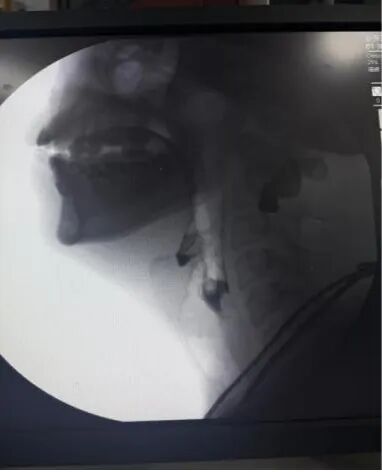

我院五疗康复科成功开展吞咽造影检查新技术:吞咽障碍诊断的“金标准”——吞咽造影检查(VFSS)

近日,我院五疗康复科联合医学影像科开展了院内首例吞咽障碍诊断的“金标准”吞咽造影检查(VFSS),并为多名脑血管病合并吞咽障碍患者完成吞咽造影检查,此项技术的开展标志着我院在吞咽障碍评估手段日趋完善,康复诊断更加精准,康复评定工作更上一层楼,为治疗吞咽障碍患者带来了福音和希望。

吞咽造影检查(VFSS)是在X线透视下,针对口、咽、喉、食管的吞咽运动所进行的吞咽检查,是目前公认最全面、可靠、有价值的吞咽功能检查法,是诊断吞咽障碍首选和理想的方法,是客观评价吞咽障碍的“金标准”,对指导临床吞咽障碍治疗具有重要意义。